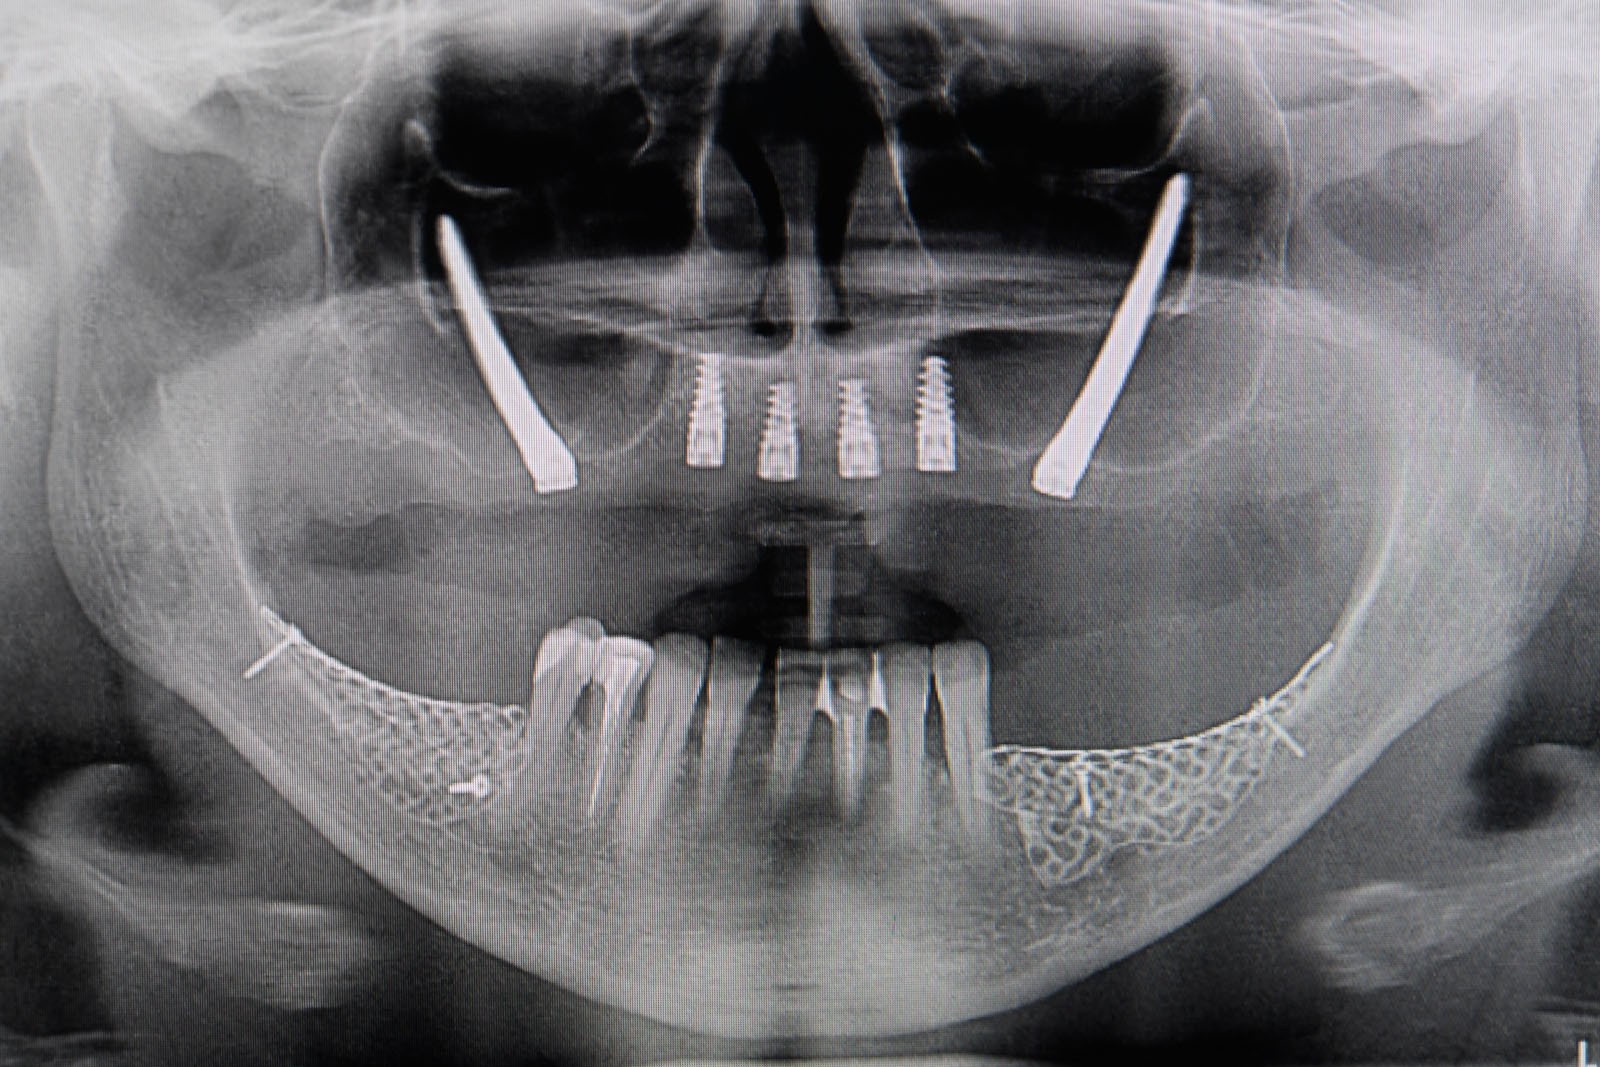

Przed podjęciem leczenia należy określić stopień zaniku kości szczęk oraz żuchwy. W tym celu przeprowadza się badanie kliniczne oraz odpowiednią diagnostykę obrazową pacjenta. Uwzględnia ona zdjęcie panoramiczne OPG jako podstawę dwuwymiarowego obrazowania podłoża kostnego oraz możliwe jest badanie tomograficzne CT lub bardziej precyzyjna tomografia stożkowa CBCT. Opcjonalnie wykorzystywana diagnostycznie tomografia pozwala na bardziej wnikliwą ocenę stopnia zaniku kości w trójwymiarowym, przestrzennym obrazie.

Zabiegiem, który rozwiązuje ten problem, jest podniesienie dna zatoki szczękowej, czyli odbudowa kostna w okolicy zębów trzonowych. Ubytek kości uzupełniany jest materiałem kościotwórczym, który układany jest pod błoną wyścielającą zatokę szczękową, zwaną membraną Schneidera. Zmniejszając objętość zatoki szczękowej, tworzy się tym samym stabilną strukturę kostną, umożliwiającą zabieg implantacji wszczepów śródkostnych.

Zatoki szczękowe to symetrycznie umieszczone w kościach szczęk przestrzenie powietrzne, posiadające komunikację z jamą nosa. Średnio pojemność zatok wynosi 24 cm3, a ściany wyścielone są błoną śluzową (membrana Schneidera). Dno zatoki szczękowej stanowi wyrostek zębodołowy, w którym umieszczone są zęby, często zlokalizowane tuż pod cienką wyściółką zatoki. Statystycznie najwęższy obszar kostny w tej strefie zlokalizowany jest na wysokości zębodołów pierwszego i drugiego zęba trzonowego.

• Metoda otwarta – opisana w 1980 przez Jamesa i Boyna – polega na chirurgicznym dostępie do zatoki szczękowej poprzez jej boczną ścianę, następnie delikatnej preparacji, oddzieleniu wyściółki (błony Schneidera) bez jej perforacji, umieszczeniu pomiędzy nią a dnem zatoki materiału odbudowującego kość. Zabieg podniesienia dna zatoki szczękowej może przebiegać z jednoczesnym wszczepieniem implantów lub wszczepieniem ich w czasie odroczonym o 6–8 miesięcy. Warunkiem jednoczesnego wszczepienia implantów jest możliwość pierwotnie stabilnego ich umocowania w pozostałej własnej kości wyrostka zębodołowego. Najmniejsza jej ilość wg niektórych autorów to 1 mm.

Ta szczególna metoda używana jest w obszarze dolnego łuku zębowego w sytuacji braku dostatecznej ilości kości na wysokość. Metoda stosowana jest w sytuacji rozległych zaników kostnych w bocznych odcinkach żuchwy, w której wprowadzenie implantów groziłoby uszkodzeniem gałązek nerwowych nerwów zębodołowych dolnych. Gałązki nerwowe biegną wraz z naczyniami krwionośnymi we wspólnej pochewce w kanałach kostnych, umieszczonych symetrycznie po obu stronach w trzonach żuchwy.

Technika polega na chirurgicznym ich przemieszczeniu, a przez to stworzeniu bezpiecznego miejsca dla wszczepienia implantów o odpowiednej długości, co gwarantuje ich stabilną pozycję. Stosuje się ją wraz z zabiegiem rekonstrukcji kostnej przy użyciu biomateriałów w formie granulatu i membran. Zabieg ten stosowany jest rzadko, jako alternatywa rozległych regeneracji kostnych. Wybierany bywa jako alternatywa operacyjna tylko w sytuacji, gdy konwencjonalne metody odbudowy kostnej są niewystarczające lub generują ryzyko braku skutecznej odbudowy kostnej celem wszczepienia implantu.